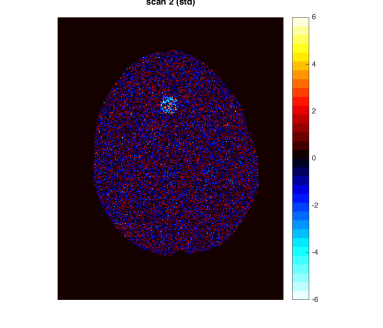

As a motivating example that will be detailed in Section 5, Figure 1 shows data from the phantom experiment in Qin et al., (2017) simulating pre- and post-treatment scans with a tumor lesion. A direct voxelwise difference between the two scans shows a global non-homogeneous background change while failing to detect changes in the lesion (Figure 1, Row 1 and Column 3). This observation suggests that background adjustment is necessary in voxelwise comparisons to reduce confounding by tissue-dependent changes not related to the disease, in order to isolate localized differences that are relevant to assess the disease status.

In the first half of this paper, we study the standardization of a Gaussian mixture model systematically in various but simple ways. We show that, surprisingly, the tail distribution of the standardized scores is favorably close to standard normal in a wide range of scenarios while being conservative at the tails, making it suitable for statistical inference. Compared to the standardization method for background adjustment in Guo et al., (2014) and Qin et al., (2017), we consider several variations using both soft and hard assignment of the observations to latent classes. In the data application in Figure 1, the analysis based on the model-based standardized differences proposed in this paper is successful (Row 2 and Column 3) as the background difference is now randomly distributed around zero and the lesion change is clearly visible; see Section 5 for more details. The distributions of the corresponding standardized scores are evaluated here theoretically, numerically and via simulations. Theoretically, it is shown that the standardized scores are indeed close to standard normal under a variety of extreme parameter settings. In non-extreme parameter settings, it is shown numerically that the soft assignment methods lead to conservative tail probabilities, making them valid for hypothesis testing purposes. It is also shown that the tail probabilities are not very sensitive to the class probabilities, which is an advantage as these are hard to estimate in practice.

In this section, we provide more details about the PET data application discussed in the Introduction (Figure 1). We use the data produced by the lesion change detection study in (Qin et al.,, 2017) using the Hoffman 3-D brain phantom (Hoffman et al.,, 1991), which simulates pre- and post-treatment scans with a tumor lesion. As described there, the brain phantom was filled with FDG radioactive fluid and PET scans were acquired on a GE Discovery ST PET-CT scanner. A malignant lesion was simulated within the central gray matter at a location superior and anterior within the brain, by placing a 1.5 cm diameter sphere of FDG. The tumor-to-background-ratio (TBR) for Scan 1 was 2:1, which was changed to 1.5:1 for Scan 2. Due to the physical construction of the phantom, these two TBR levels were achieved by increasing the activity in the phantom background rather than changing the activity in the lesion (injecting more radio-tracer to the background, while keeping the activity concentration in the lesion constant), effectively producing a reduction in the lesion activity with respect to the background. Image registration was performed between the two scans. The first row of Figure 1 shows one slice of the two scans and their difference (same slice as in Qin et al., (2017)).

By design, there is a large background change but no change in the lesion. A direct difference between the two scans shows a global non-homogeneous background change while failing to detect changes in the lesion (Figure 1, Row 1 and Column 3). In contrast, the analysis based on the model-based standardized differences proposed in this paper is successful (Figure 1, Row 2 and Column 3). Specifically, the second row shows the standardized scores using the proposed robust EM algorithm RB-SGMM and background adjustment via the soft-assignment transformation . The estimated background parameters are those given in (4.1). The standardized scores show a distribution close to standard normal with little anatomical structure except for the lesion. The standardized difference in the third column again has a distribution close to standard normal and exhibits the lesion change clearly at -6 standard deviations away from 0.